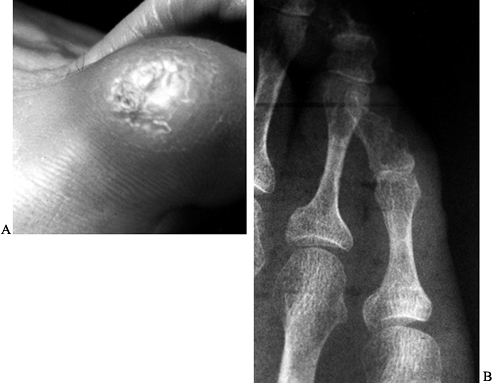

Figure 113.1. A patient with a symptomatic second hammer toe. A: Oblique view. B: Top view.